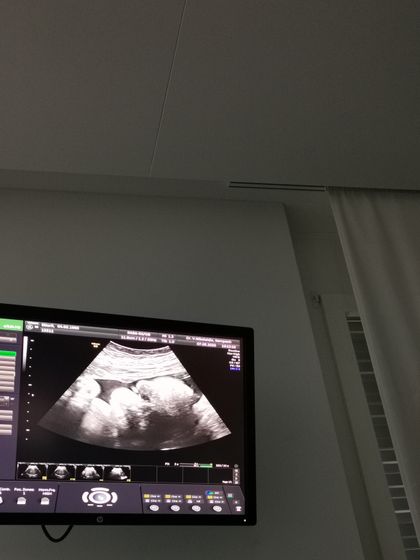

Вчера было ровно 35 недель, аж не верится ?. В эту беременность время летит очень быстро. 3 дня назад были на плановом приеме у гини. Посмотрели нашего сладкого мальчика, все у него отлично. Самая главная новость ОН ПЕРЕВЕРНУЛСЯ ? как же я рада ❤️.

Вес сыночка 2700

Рост 47 см.